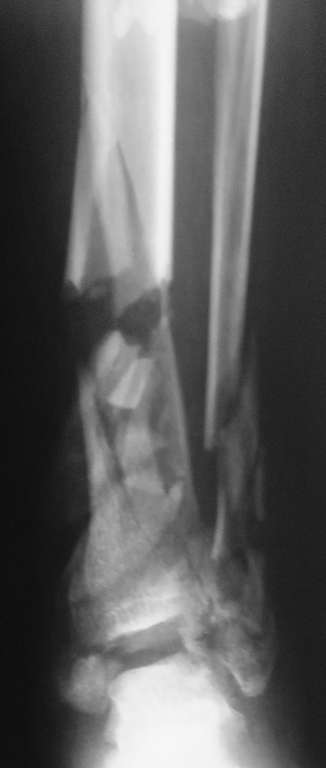

Перелом пилона

Пациент, 22 года, травму получил в результате ДТП (управление мотоциклом). Имеет место открытый оскольчатый перелом костей левой голени в нижней трети.Хотелось бы узнать Ваши мнения по лечению данного пациента.

То примеры, а то практика. Конверсия аппрата на гвоздь - технология избыточная в большинстве случаев!!, не всегда, конечно. Но в данном-то случае какой гвоздь? Речь идёт о восстановлении сустава, а не только об удобстве фиксации. Забейте сюда гвоздь - что, больной встанет и пойдёт на этом гвозде? Сустав разрушен, это видно и по единственному снимку (кстати, почему единственному? - 2 автор). Да открытый перелом. Да несвежий. Да... В-общем, аппаратом надо лечить. Вот только по 1 снимку не ясно, можно ли создать наружный щит сустава.

Надо выставить все возможные рентгенологические данные с описанием состояния мягких тканей. Для планирования операции при переломах пилона кроме рентгена также важны исследования на Компьютерной Томографии.